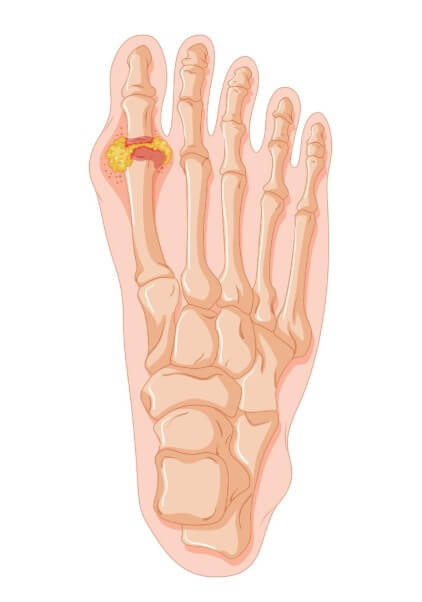

무지외반증은 단순한 미용 문제가 아닌, 걸을 때의 통증과 관절 기능 저하로 일상생활에 큰 불편을 주는 질환입니다. 다양한 수술 방법이 존재하며, 환자의 증상 정도, 뼈의 변형 각도, 나이, 활동 수준 등에 따라 적합한 수술법이 달라집니다. 이 글에서는 무지외반증 환자가 꼭 알아야 할 주요 수술법들을 구조적으로 정리해 설명합니다.

수술을 결정하기 전에는 정확한 진단과 영상 검사로 변형의 각도, 관절 안정성, 발의 구조적 특징을 파악해야 합니다. 무조건 절골술을 우선으로 보기보다, 환자의 나이, 활동성, 생활습관, 수술 후 기대 등을 고려해 가장 적합한 방법을 선택하는 것이 핵심입니다. 무지외반증은 환자 개인별로 매우 다양한 양상을 보이는 만큼, 족부 전문의와의 충분한 상담이 필요합니다.